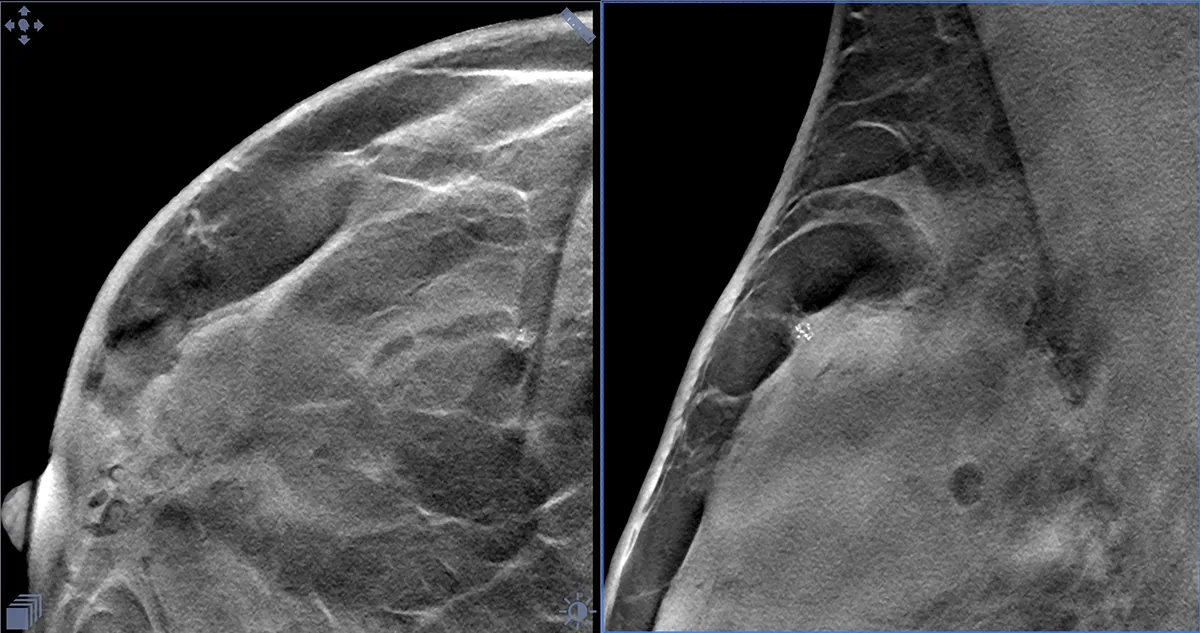

Ранее, во времена радикального, но не онкопластического подхода при лечении рака молочной железы, в таких случаях выполняли мастэктомию. Этой пациентке врач-маммолог, онкопластический хирург Оксана Васильевна Шулига-Недайхлебова первым этапом лечения предложила плановое оперативное вмешательство в объеме онкопластической лампэктомии правой МЗ с интраоперационным гистологическим исследованием чистоты краев резекции, биопсией сторожевых лимфоузлов. Учитывая специфичность образования, на предоперационном этапе breast-радиологом была установлена метка-локалайзер (фото) в участок микрокальцинатов под контролем маммографии.

Интраоперационно был выполнен рентгенконтроль удаленного сектора МЗ. Рентгенография интраоперационного материала установила, что патологически измененная ткань полностью удалена. Но в целях двойного и надежного контроля материал также отправлен на срочное (экспресс) морфологическое исследование чистоты краев резекции после цветовой маркировки. В заключении интраоперационного гистологического исследования рентгенологически данные радикального удаления опухоли подтверждены. Проведено дополнительное иссечение краев резекции и отправлено на экспресс морфологическое исследование – пока не получен результат чистых краев резекции дважды.